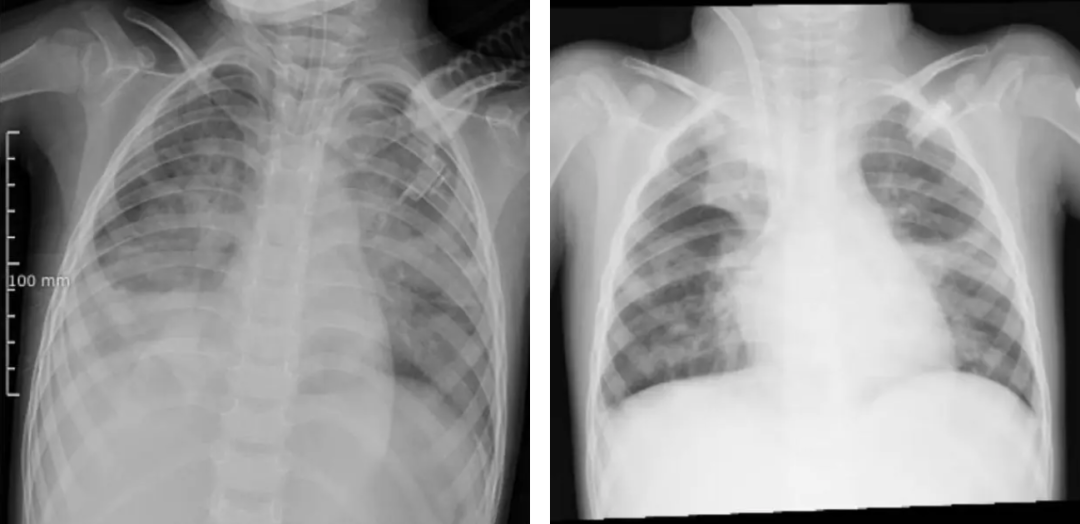

圖源河南省兒童醫(yī)院(左圖為ECMO上機(jī)前,肺部結(jié)構(gòu)模糊,呈現(xiàn)“白肺”影像表現(xiàn)。右圖為ECMO支持治療5天后,肺部影像清晰度明顯改善)

檢查結(jié)果令人揪心:甲型流感病毒(H3N2)、金黃色葡萄球菌、流感嗜血桿菌,形成“病毒牽頭、細(xì)菌跟攻”的“三重打擊”,引發(fā)嚴(yán)重肺部感染,發(fā)展為急性呼吸窘迫綜合征(ARDS),生命懸于一線。

當(dāng)?shù)蒯t(yī)院醫(yī)療團(tuán)隊(duì)幾乎使用了所有常規(guī)治療手段:有創(chuàng)呼吸機(jī)、高頻振蕩通氣、一氧化氮吸入……然而,即使在極高的呼吸機(jī)參數(shù)支持下,朵朵的血氧飽和度仍僅能維持在80%-85%,呼吸衰竭難以糾正。

在常規(guī)治療無(wú)效、命懸一線之際,河南省兒童醫(yī)院ECMO團(tuán)隊(duì)攜“人工肺”緊急跨市馳援,成功建立生命通道,完成了一場(chǎng)與時(shí)間賽跑的生死救援。上機(jī)一周后,經(jīng)全面評(píng)估各項(xiàng)指標(biāo),朵朵順利撤離ECMO,轉(zhuǎn)入后續(xù)康復(fù)治療階段。